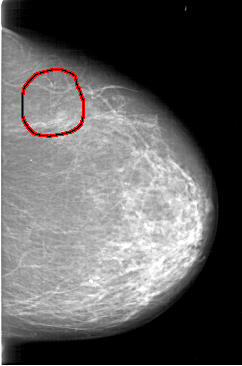

D_4198_1.RIGHT_CC

LEFT_CC LINES 6571 PIXELS_PER_LINE 4351 BITS_PER_PIXEL 12 RESOLUTION 43.5 OVERLAY

FILE: D_4198_1.LEFT_CC.OVERLAY

TOTAL_ABNORMALITIES 1

ABNORMALITY 1

LESION_TYPE CALCIFICATION TYPE ROUND_AND_REGULAR-PLEOMORPHIC DISTRIBUTION CLUSTERED

ASSESSMENT 0

SUBTLETY 4

PATHOLOGY BENIGN

TOTAL_OUTLINES 1

BOUNDARY